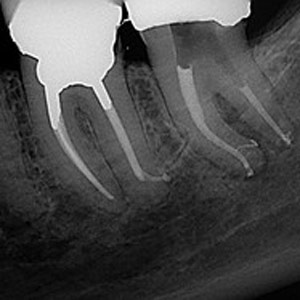

NON-SURGICAL

Oftentimes, our patients need non-surgical treatments that require minimal intervention. This intertwines with our belief that preventative maintenance and regular dental care can minimize the need for surgeries. You can rest assured that our highly trained and experienced team consistently provides the highest quality endodontic treatments and assistance available in the North Shore.